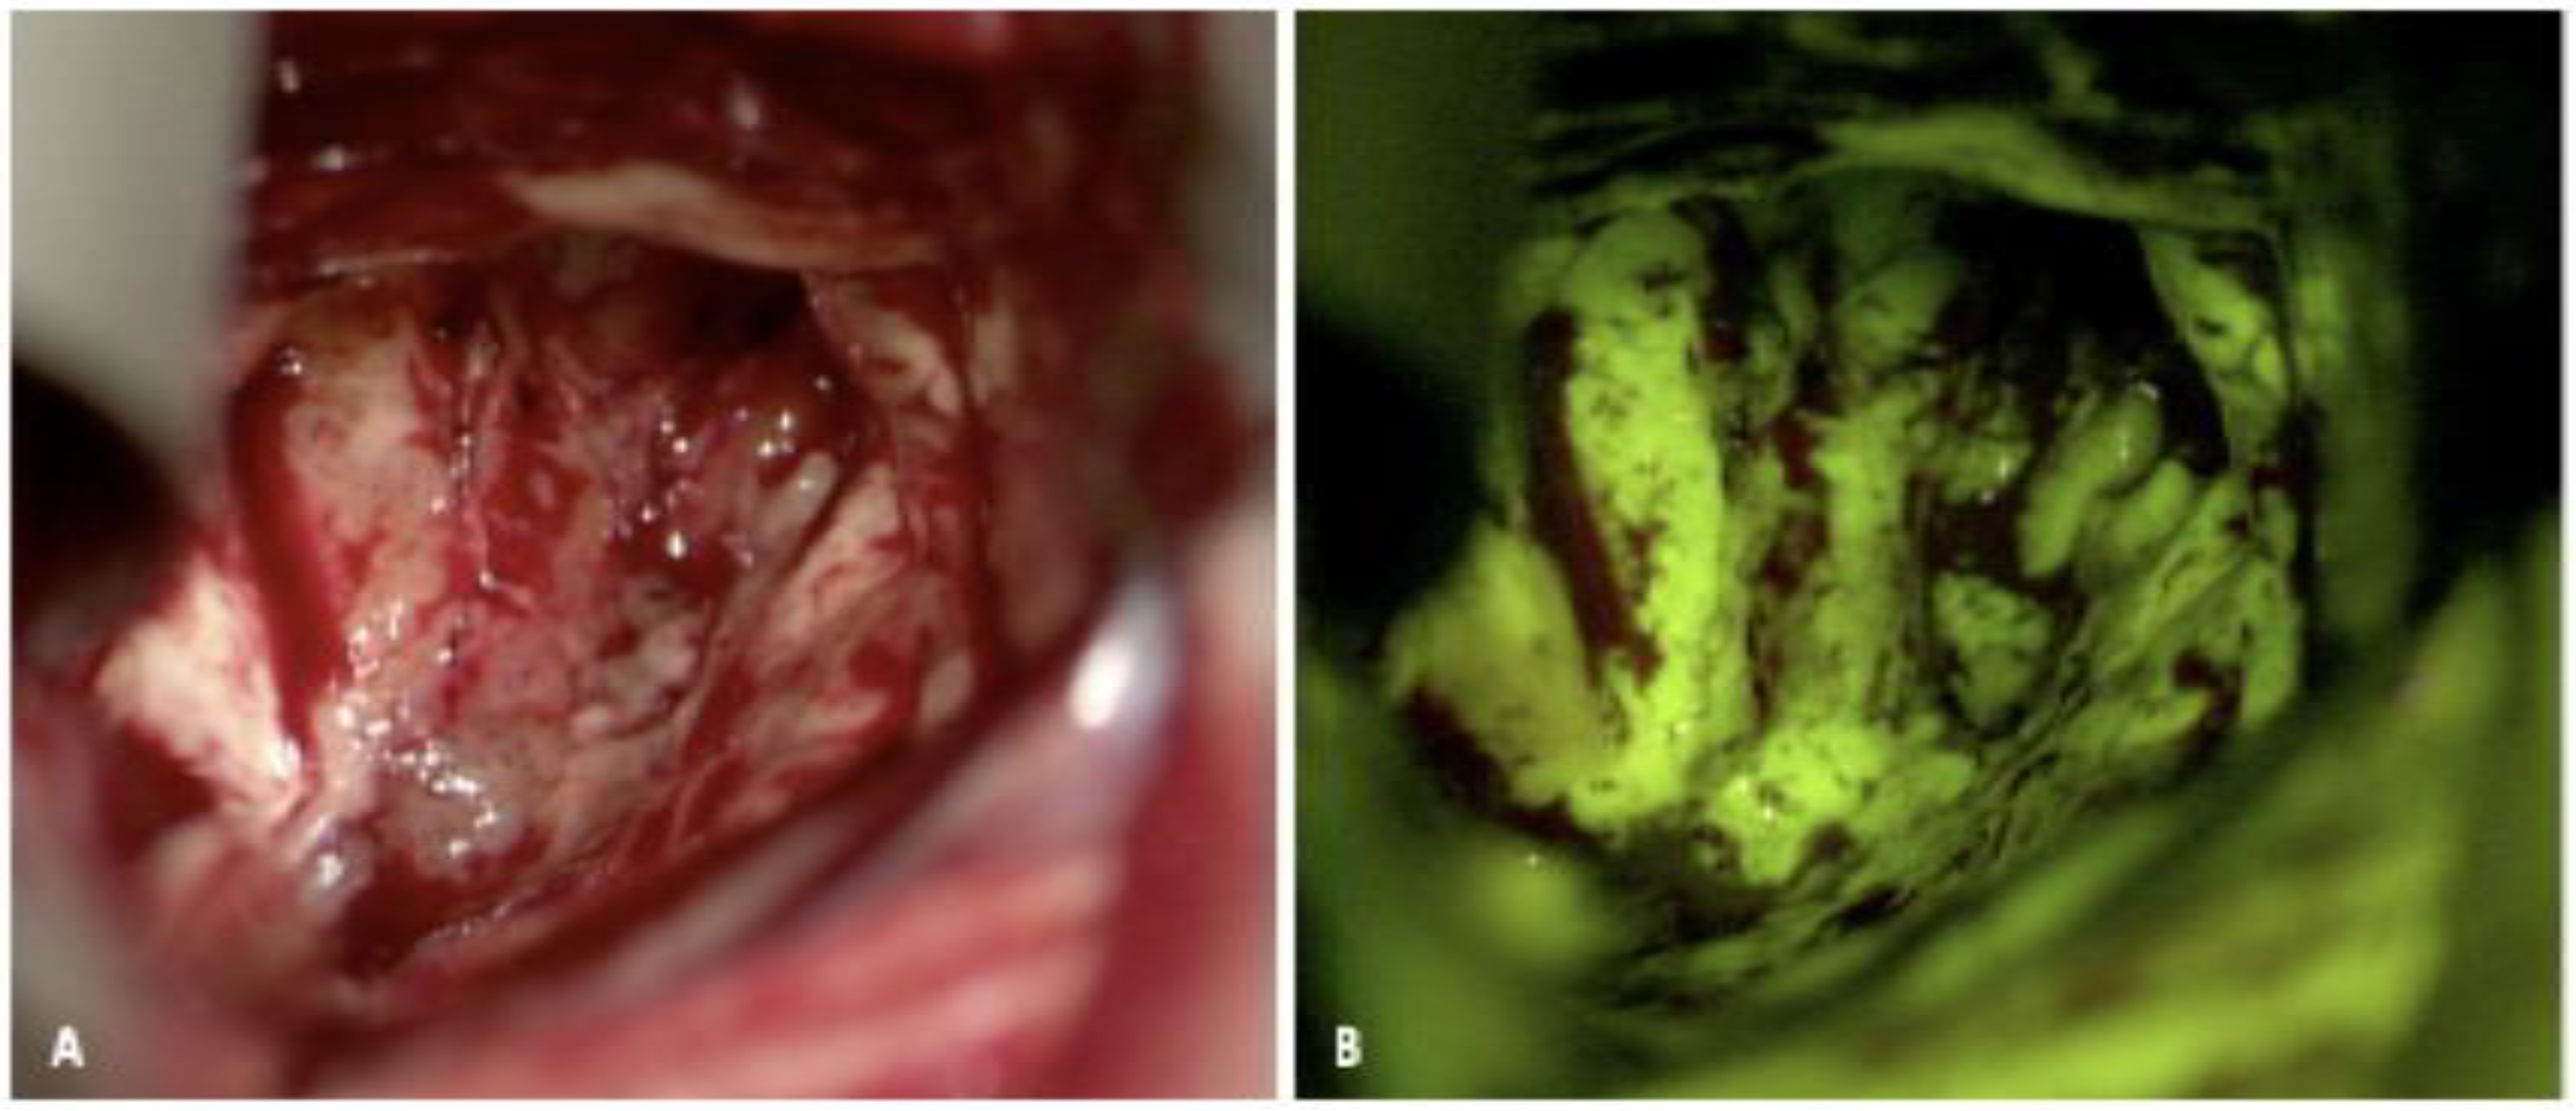

2.3. ICG

2.3.1. ICG: Background and Mechanism of Action

2.3.2. ICG: Evidence for Use

2.3.3. ICG: Limitations